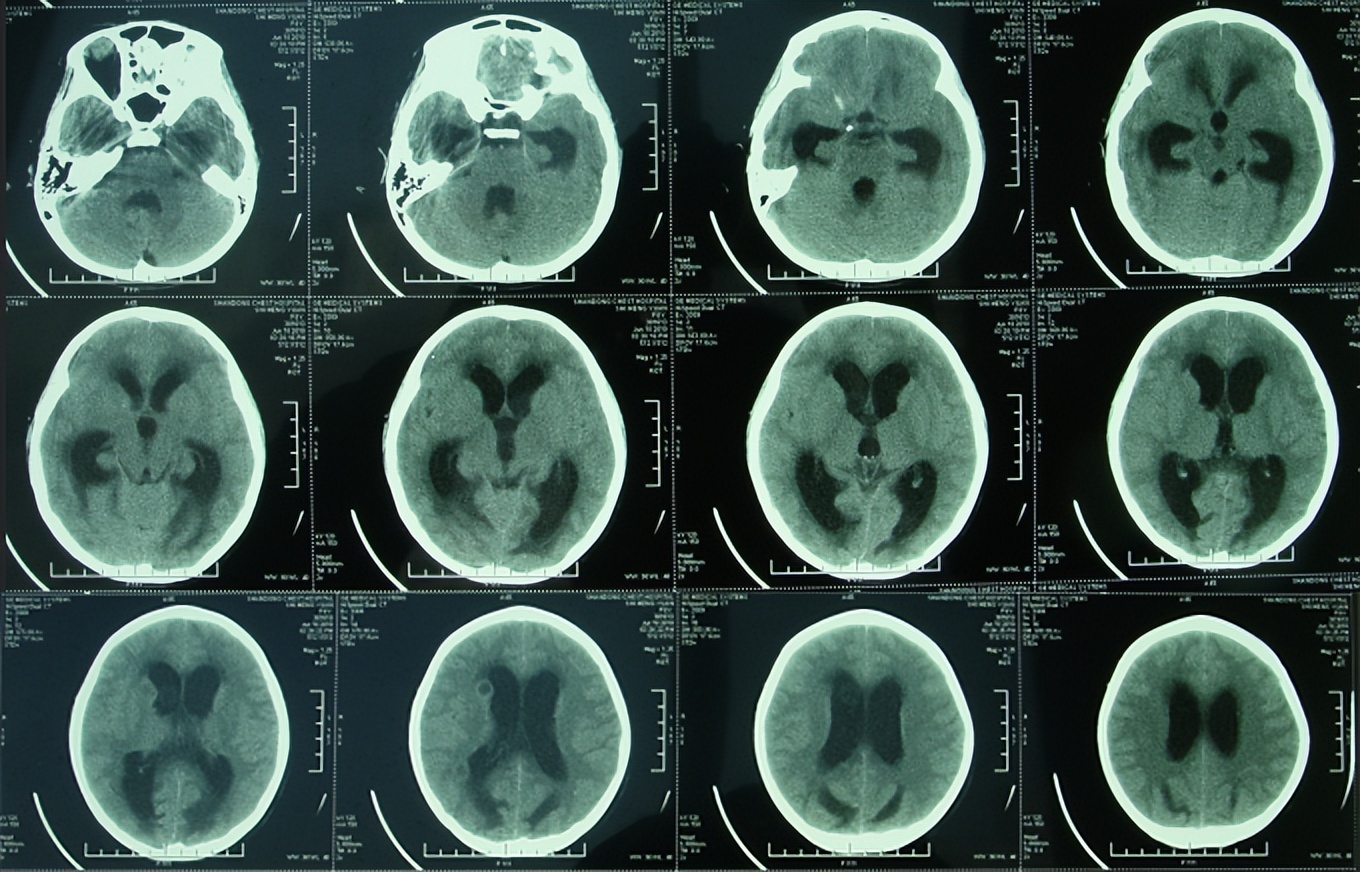

2010年6月9日(治疗17天),突发癫痫大发作,医生下病危通知书。当日复查核磁(图-2)发现脑室有扩张,中度脑积水和脑内多发脑脓肿。

图-2:2010年6月9日头颅核磁

在2010年6月10日转入第3家医院给予结核性脑膜炎的治疗,在1周后即在2010年6月18日进行了脑CT的检查(图-3)示脑室进一步扩大,“因侧脑室旁的2个病灶的显示,证实了结核性脑膜炎的诊断”。

图-3:2010年6月18日头颅CT